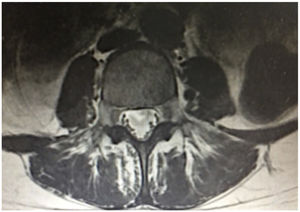

Descripción del casoPaciente femenina de 24 años sin antecedentes de relevancia, quien consulta por cuadro clínico de 15 días de evolución consistente en fiebre intermitente entre 39-40°C asociada a malestar general, astenia, adinamia, dolor dorsolumbar intenso, escala análoga del dolor 10/10, con posterior paraparesia progresiva que dificulta la marcha y la bipedestación, asociado a retención urinaria. En el examen físico presenta paraparesia arrefléxica de miembros inferiores con fuerza proximal 0/5, distal 3/5 y Babinski bilateral con nivel sensitivo en T12. El resto del examen físico no presentaba anormalidades. Se realiza resonancia magnética cerebral que no muestra lesiones intra o extraparenquimatosas; la resonancia magnética de columna dorsolumbar evidencia irregularidad en la intensidad de la señal del saco dural con realce anormal leptomeníngeo desde T3-T4 hasta el cono medular con realce a nivel del origen de las raíces, además de agrupamiento de estas como signos de aracnoiditis (fig. 1), y electromiografía y neuroconducción de miembros inferiores donde se documenta polirradiculopatía lumbosacra bilateral de L3-S1. Se realiza punción lumbar, en la cual se evidencia hipertensión intracraneana, citoquímico de LCR con pleocitosis de predominio mononuclear, hipoglucorraquia e hiperproteinorraquia; tinciones directas negativas incluyendo baciloscopia, pero con prueba molecular (GeneXpert®) para TB positiva y test de ADA elevado (tabla 1), por lo cual se hace el diagnóstico de mielorradiculitis por TB. Se inicia tratamiento antituberculoso tetraconjugado (isoniazida, rifampicina, etambutol y pirazinamida).

Los cambios característicos de la resonancia magnética indicativos de aracnoiditis espinal incluyen loculaciones del LCR y obliteración del espacio subaracnoideo espinal, así como realce nodular, grueso, lineal, intradural y pérdida del contorno de la médula espinal en la región cervicotorácica, junto con el enmarañado de las raíces nerviosas en la zona lumbar8. La mielitis tuberculosa aparece como señal hiperintensa en T2, isointensa a hipointensa en las imágenes ponderadas en T1 y muestra un realce segmentario en las imágenes poscontraste15.

Gupta et al. en el 2015 documentaron en pacientes con meningitis tuberculosa con afectación medular que el 57,7% presentaban cambios en la médula espinal y/o en la raíz del nervio espinal por resonancia magnética, siendo las más frecuentes mielitis, aracnoiditis lumbosacra, tuberculoma, siringomielia, atrofia de la médula y realce meníngeo espinal, ya sea solo o en combinación. El sitio más común de afectación fue en el 32,4% la región lumbosacra, seguida en el 9,9% de la región toracolumbar12.